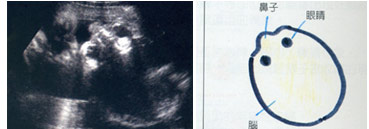

怀孕27周

怀孕27周

胎儿的脑容量已经明显增大啰!